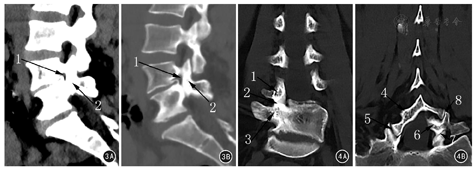

患者女,36岁,因"间断性右侧腰腿痛8年余,再次发作3个月",于2016年8月1日来海军总医院骨科就诊。曾在外院行腰椎平片及CT检查示腰骶椎隐裂(原始影像资料丢失),难以找到病痛的原因。查体:约平L4~5棘突间隙右侧压叩痛,向右下肢放射,右股神经牵拉试验阳性,右小腿内侧感觉减退,呈L4神经根受损体征。患者在我院行腰椎X线摄片检查报告示:L4~5椎间隙变窄,L5及S1隐裂。笔者阅读我院X线片,发现腰椎区域实际有以下多处形态及结构异常:正位片(图1A)示腰椎呈S形弯曲;L1~3以L2为顶椎右侧凸,似姿势性侧凸,但L3右椎板及下关节突发育肥大;右L3~4椎板间隙降至右L4椎弓根上界高度;以L4~5椎间隙为顶椎左侧凸,有多处解剖畸形。解剖畸形包括:(1)椎弓根,L4右侧椎弓根低于左侧;L4~5右侧椎间孔高度明显小于左侧。(2)横突,右侧L4横突发育小且低于左侧。(3)椎板,右侧L4及L5椎弓根向内共同发出一椎板结构,即L4~5椎板融合体,无右L4~5椎板间隙;右L4~5椎板融合体向中线上方移行,在棘突中线同左侧L4椎板融合,而左侧L5椎板游离,在中线略偏右同L4~5椎板融合体隔一左上斜向右下的裂隙,易误判为L5隐裂;右侧L4~5关节突关节辨不清。侧位片(图1B)示L4~5椎间隙变窄,L4~5椎间孔下方似有骨样突起。左斜位片(图1C)能辨出L4~5关节突关节;右斜位(图1D)示L4~5关节突关节结构消失。过伸过屈位片(图1E、图1F)示L4~5节段无活动度。腰椎CT检查及重建影像报告仅提及腰骶椎隐裂。笔者阅读CT横断面图像,未见到L3~S1节段有椎间盘突出;但对L4~5椎间隙节段的横断面连续CT图像观察发现L4~5右侧椎间孔前后径变小,自L5椎体右后缘有骨性隆起使椎间孔呈迂曲状,右侧L4~5椎板融合体宽度明显为厚(图2)。矢状位CT重建见右侧L4~5椎间孔周径明显变小,L4~5关节突关节融合(图3)。冠状位CT重建图像证实右L4~5关节突关节融合,右侧L4椎弓根平面下降,右侧L4横突发育不良,右侧L4~5椎板融合(图4)。患者经卧床休息、脱水及激素冲击治疗,右侧下肢放射痛减轻。建议行腰椎MR或腰椎管造影了解神经根走行有无异常,患者因症状缓解拒绝再行进一步检查。随访3个月,期间右侧下肢放射痛复发1次,但未达到3个月前强度,口服镇痛消肿药物及卧床休息后,症状再次好转。患者暂未手术,继续随访观察中。